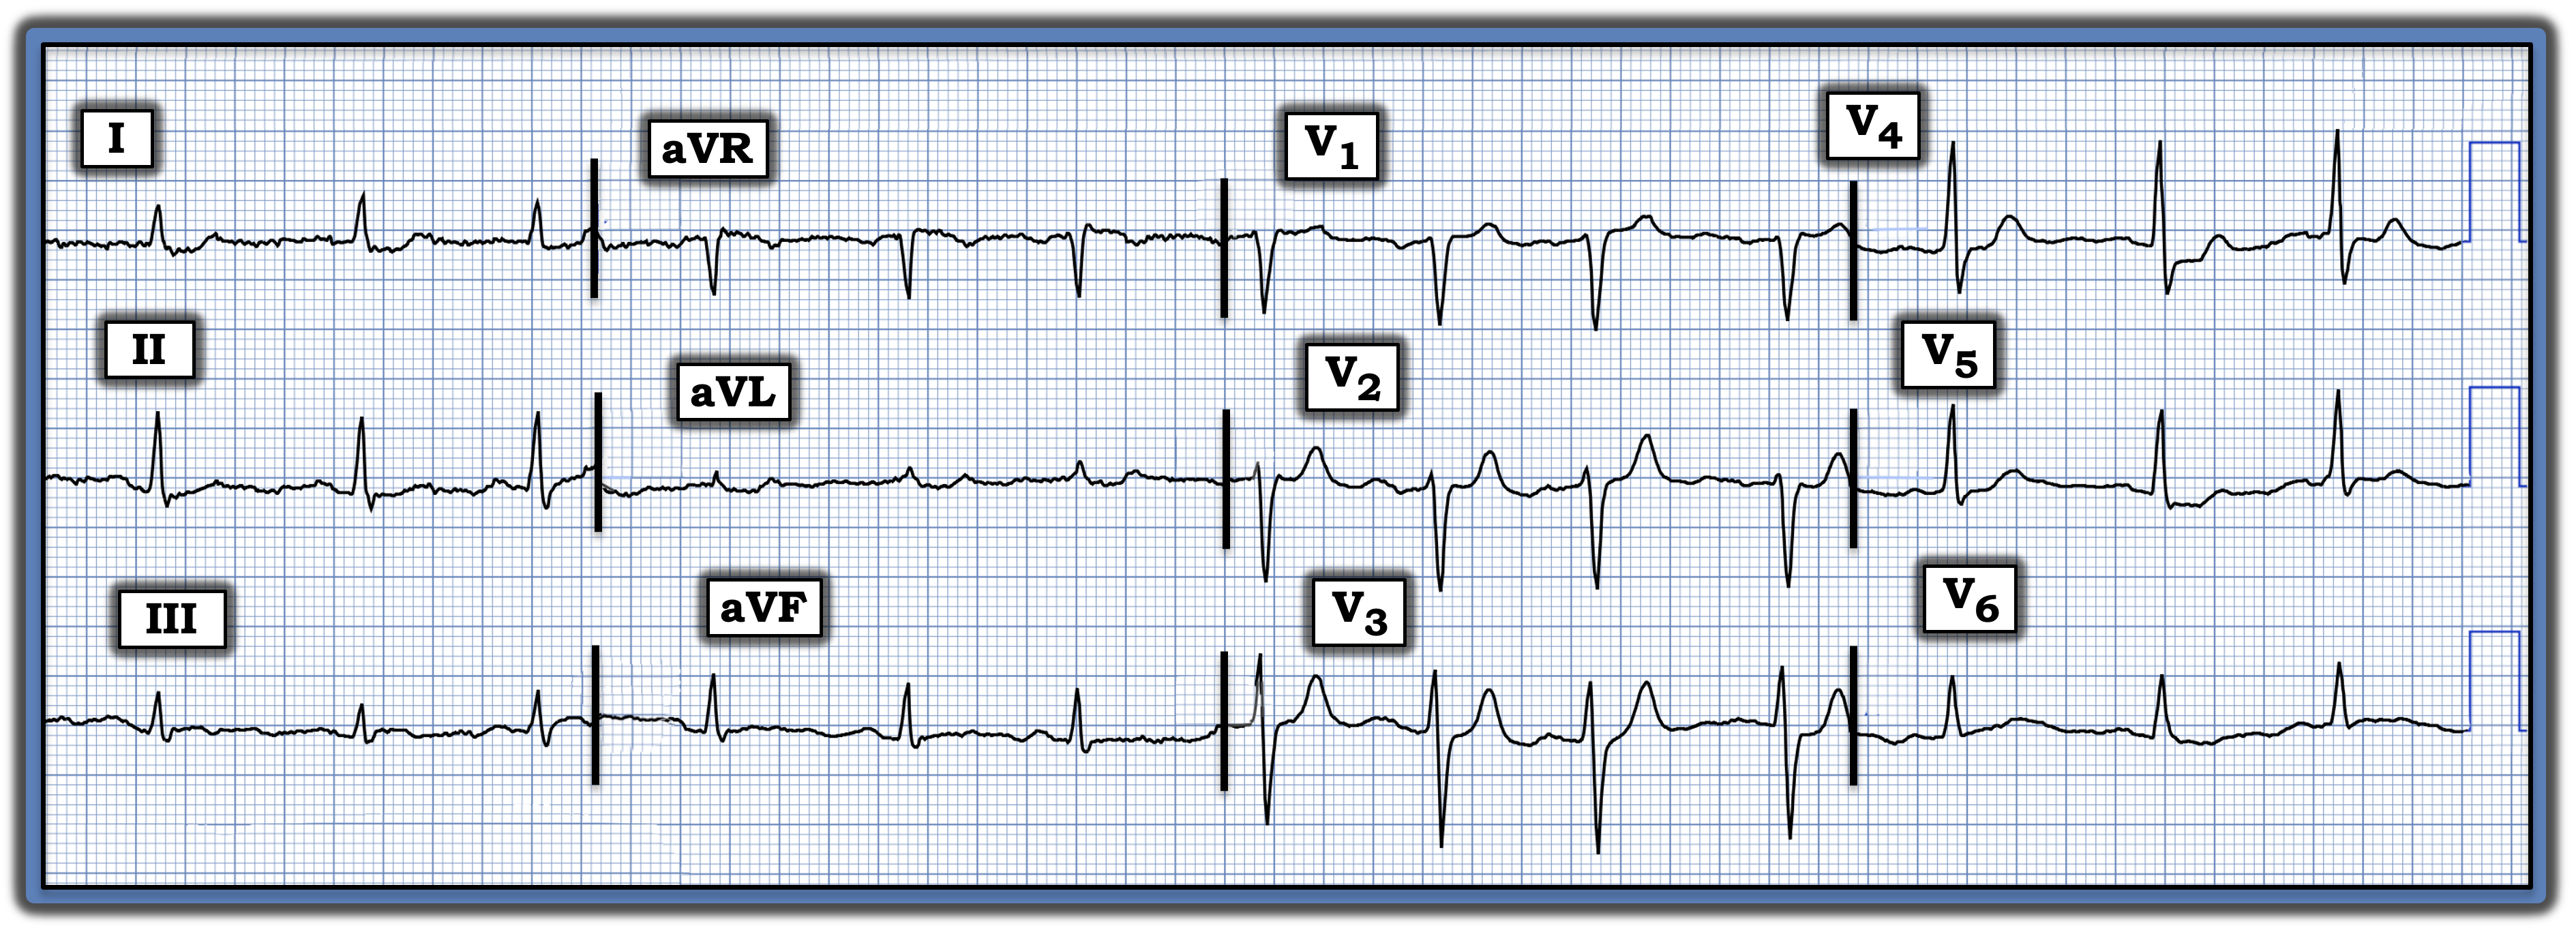

The electrocardiogram (ECG) in the figure is from a man with a new and severe “burning” chest discomfort. On seeing this ECG, the paramedic team requested activating the cath lab. Would you have done the same?

Interpretation: The ECG in the figure shows a normal sinus rhythm at ~85 beats/minute. All intervals (PR, QRS, QTc) and the axis are normal. There is no chamber enlargement. There are no Q waves, and R wave progression is normal.

The key findings are subtle-but-real ST-T wave abnormalities in a number of leads. Those, in association with the patient history, should prompt significant concern.

- Normally, there should be slight, gently upsloping ST elevation in anterior leads V2 and V3. Instead, the ST segment in lead V2 appears straightened with, if anything, a slight ST depression in neighboring lead V3. In addition, the T wave in lead V2 (if not also in lead V3) looks disproportionately taller than it should be, given R wave amplitude in these respective leads.

To emphasize, the previously noted ST-T wave changes in leads V2 and V3 are extremely subtle. That said, there can be no doubt that the ST segment straightening and depression seen in lead V4 is real and supports the validity of our suspicion regarding the subtle abnormalities noted in leads V2 and V3.

- Additional ST-T wave findings of potential concern include nonspecific ST segment flattening in multiple leads, with slight ST depression in leads I, II, and V5, and ST segment coving, with the suggestion of slight ST elevation and shallow terminal T-wave inversion in lead III.

- In today’s patient with new chest discomfort, the findings of subtle anterior lead ST segment flattening with ST depression, in association with disproportionately taller-than-expected anterior T waves plus the ST-T wave changes seen in lead III, suggest recent infero-postero OMI. The reason that frank ST elevation is missing probably is the result of spontaneous reperfusion of the “culprit” artery.

- Prompt cardiac catheterization should be considered, especially if chest discomfort persists, if serum troponin is elevated, and/or if serial ECGs suggest ongoing evolution.

- To emphasize, in a patient such as this, the initial ECG should be repeated within no more than 15 to 30 minutes after the initial tracing, since “dynamic” ST-T wave changes may occur surprisingly soon in an actively evolving process.

- Follow-up: Acute infarction was confirmed, cardiac catheterization revealed multi-vessel disease, and the patient was scheduled for coronary bypass surgery.